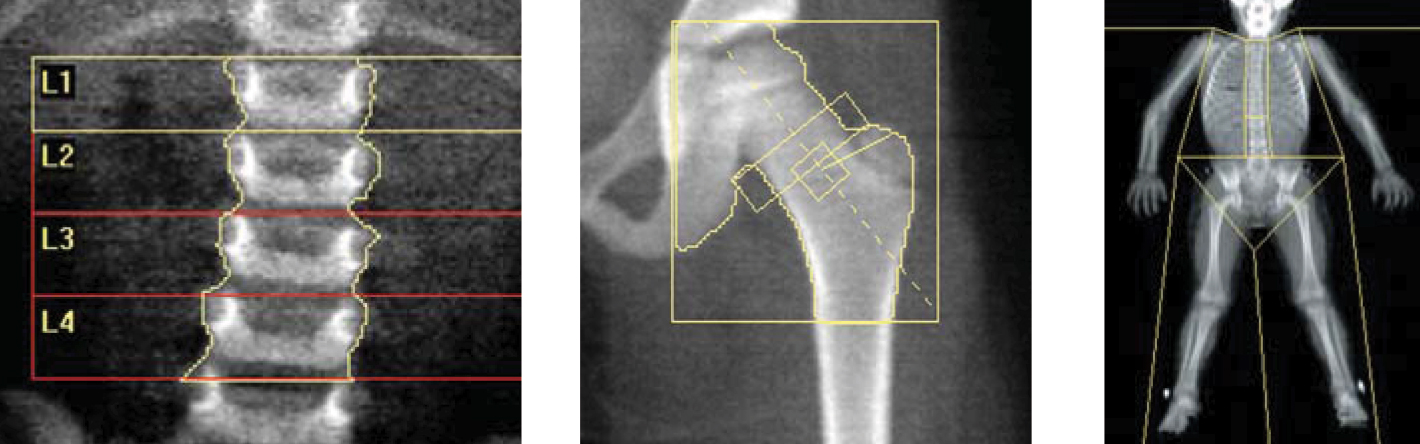

Тест для измерения минеральной плотности костной ткани называется денситометрией кости. На сегодняшний день это наиболее широко используемый метод измерения плотности костной ткани.

- Однако при ранней диагностике его останавливают там, где есть. - Измерение плотности костной ткани - очень простой процесс: система выполняет измерение за короткое время, например, за 8 минут, когда человек лежит на спине. В нашей клинике измерение плотности костной ткани выполняется с помощью нашего современного устройства марки General Electric / LUNAR.

Самый важный метод диагностики - измерение плотности костной ткани. Обследование проводится с помощью специального устройства с очень низкой дозой рентгеновского излучения. Процедура не требует подготовки или приема лекарств, занимает короткое время. Измерение плотности костной ткани проводится в нашем отделении за 10-20 минут, без предварительной подготовки, без инъекций, с компьютерной поддержкой.